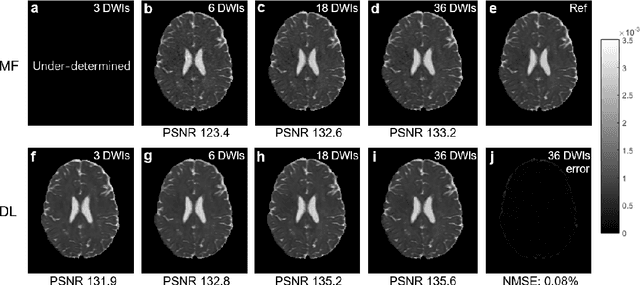

Abstract:Diffusion tensor imaging (DTI) is widely used to examine the human brain white matter structures, including their microarchitecture integrity and spatial fiber tract trajectories, with clinical applications in several neurological disorders and neurosurgical guidance. However, a major factor that prevents DTI from being incorporated in clinical routines is its long scan time due to the acquisition of a large number (typically 30 or more) of diffusion-weighted images (DWIs) required for reliable tensor estimation. Here, a deep learning-based technique is developed to obtain diffusion tensor images with only six DWIs, resulting in a significant reduction in imaging time. The method uses deep convolutional neural networks to learn the highly nonlinear relationship between DWIs and several tensor-derived maps, bypassing the conventional tensor fitting procedure, which is well known to be highly susceptible to noises in DWIs. The performance of the method was evaluated using DWI datasets from the Human Connectome Project and patients with ischemic stroke. Our results demonstrate that the proposed technique is able to generate quantitative maps of good quality fractional anisotropy (FA) and mean diffusivity (MD), as well as the fiber tractography from as few as six DWIs. The proposed method achieves a quantification error of less than 5% in all regions of interest of the brain, which is the rate of in vivo reproducibility of diffusion tensor imaging. Tractography reconstruction is also comparable to the ground truth obtained from 90 DWIs. In addition, we also demonstrate that the neural network trained on healthy volunteers can be directly applied/tested on stroke patients' DWIs data without compromising the lesion detectability. Such a significant reduction in scan time will allow inclusion of DTI into clinical routine for many potential applications.